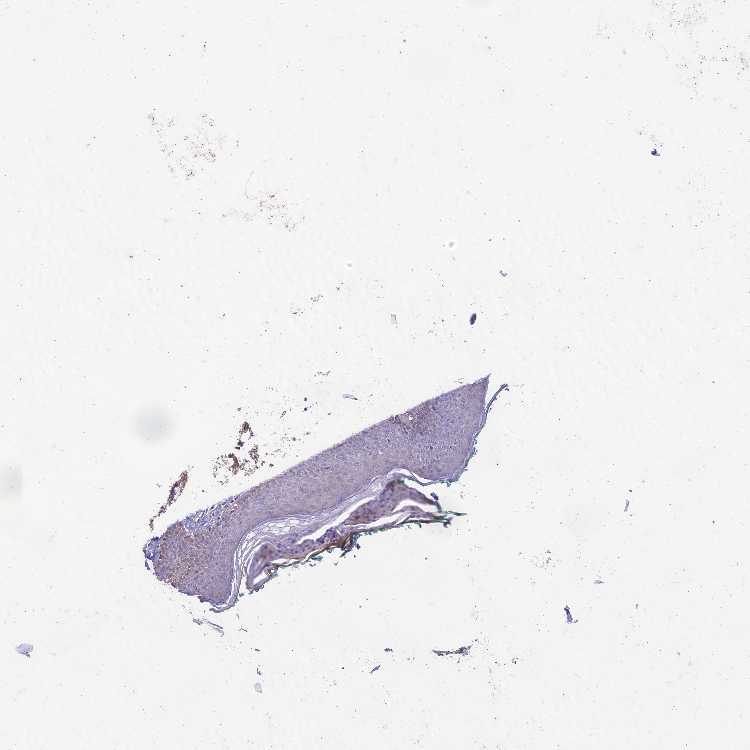

SKIN 1 - Antibody stainingi

Antibody staining in the annotated cell types in the current human tissue is reported as not detected, low, medium, or high, based on conventional immunohistochemistry profiling in selected tissues. This score is based on the combination of the staining intensity and fraction of stained cells.

Each image is clickable and will lead to virtual microscopy that enables deeper exploration of all samples and also displays staining intensity scores, fraction scores and subcellular localization as well as patient and tissue information for each sample.

Antibody HPA043686

Langerhans Not detected

Fibroblasts Not detected

Keratinocytes Not detected

Melanocytes Low